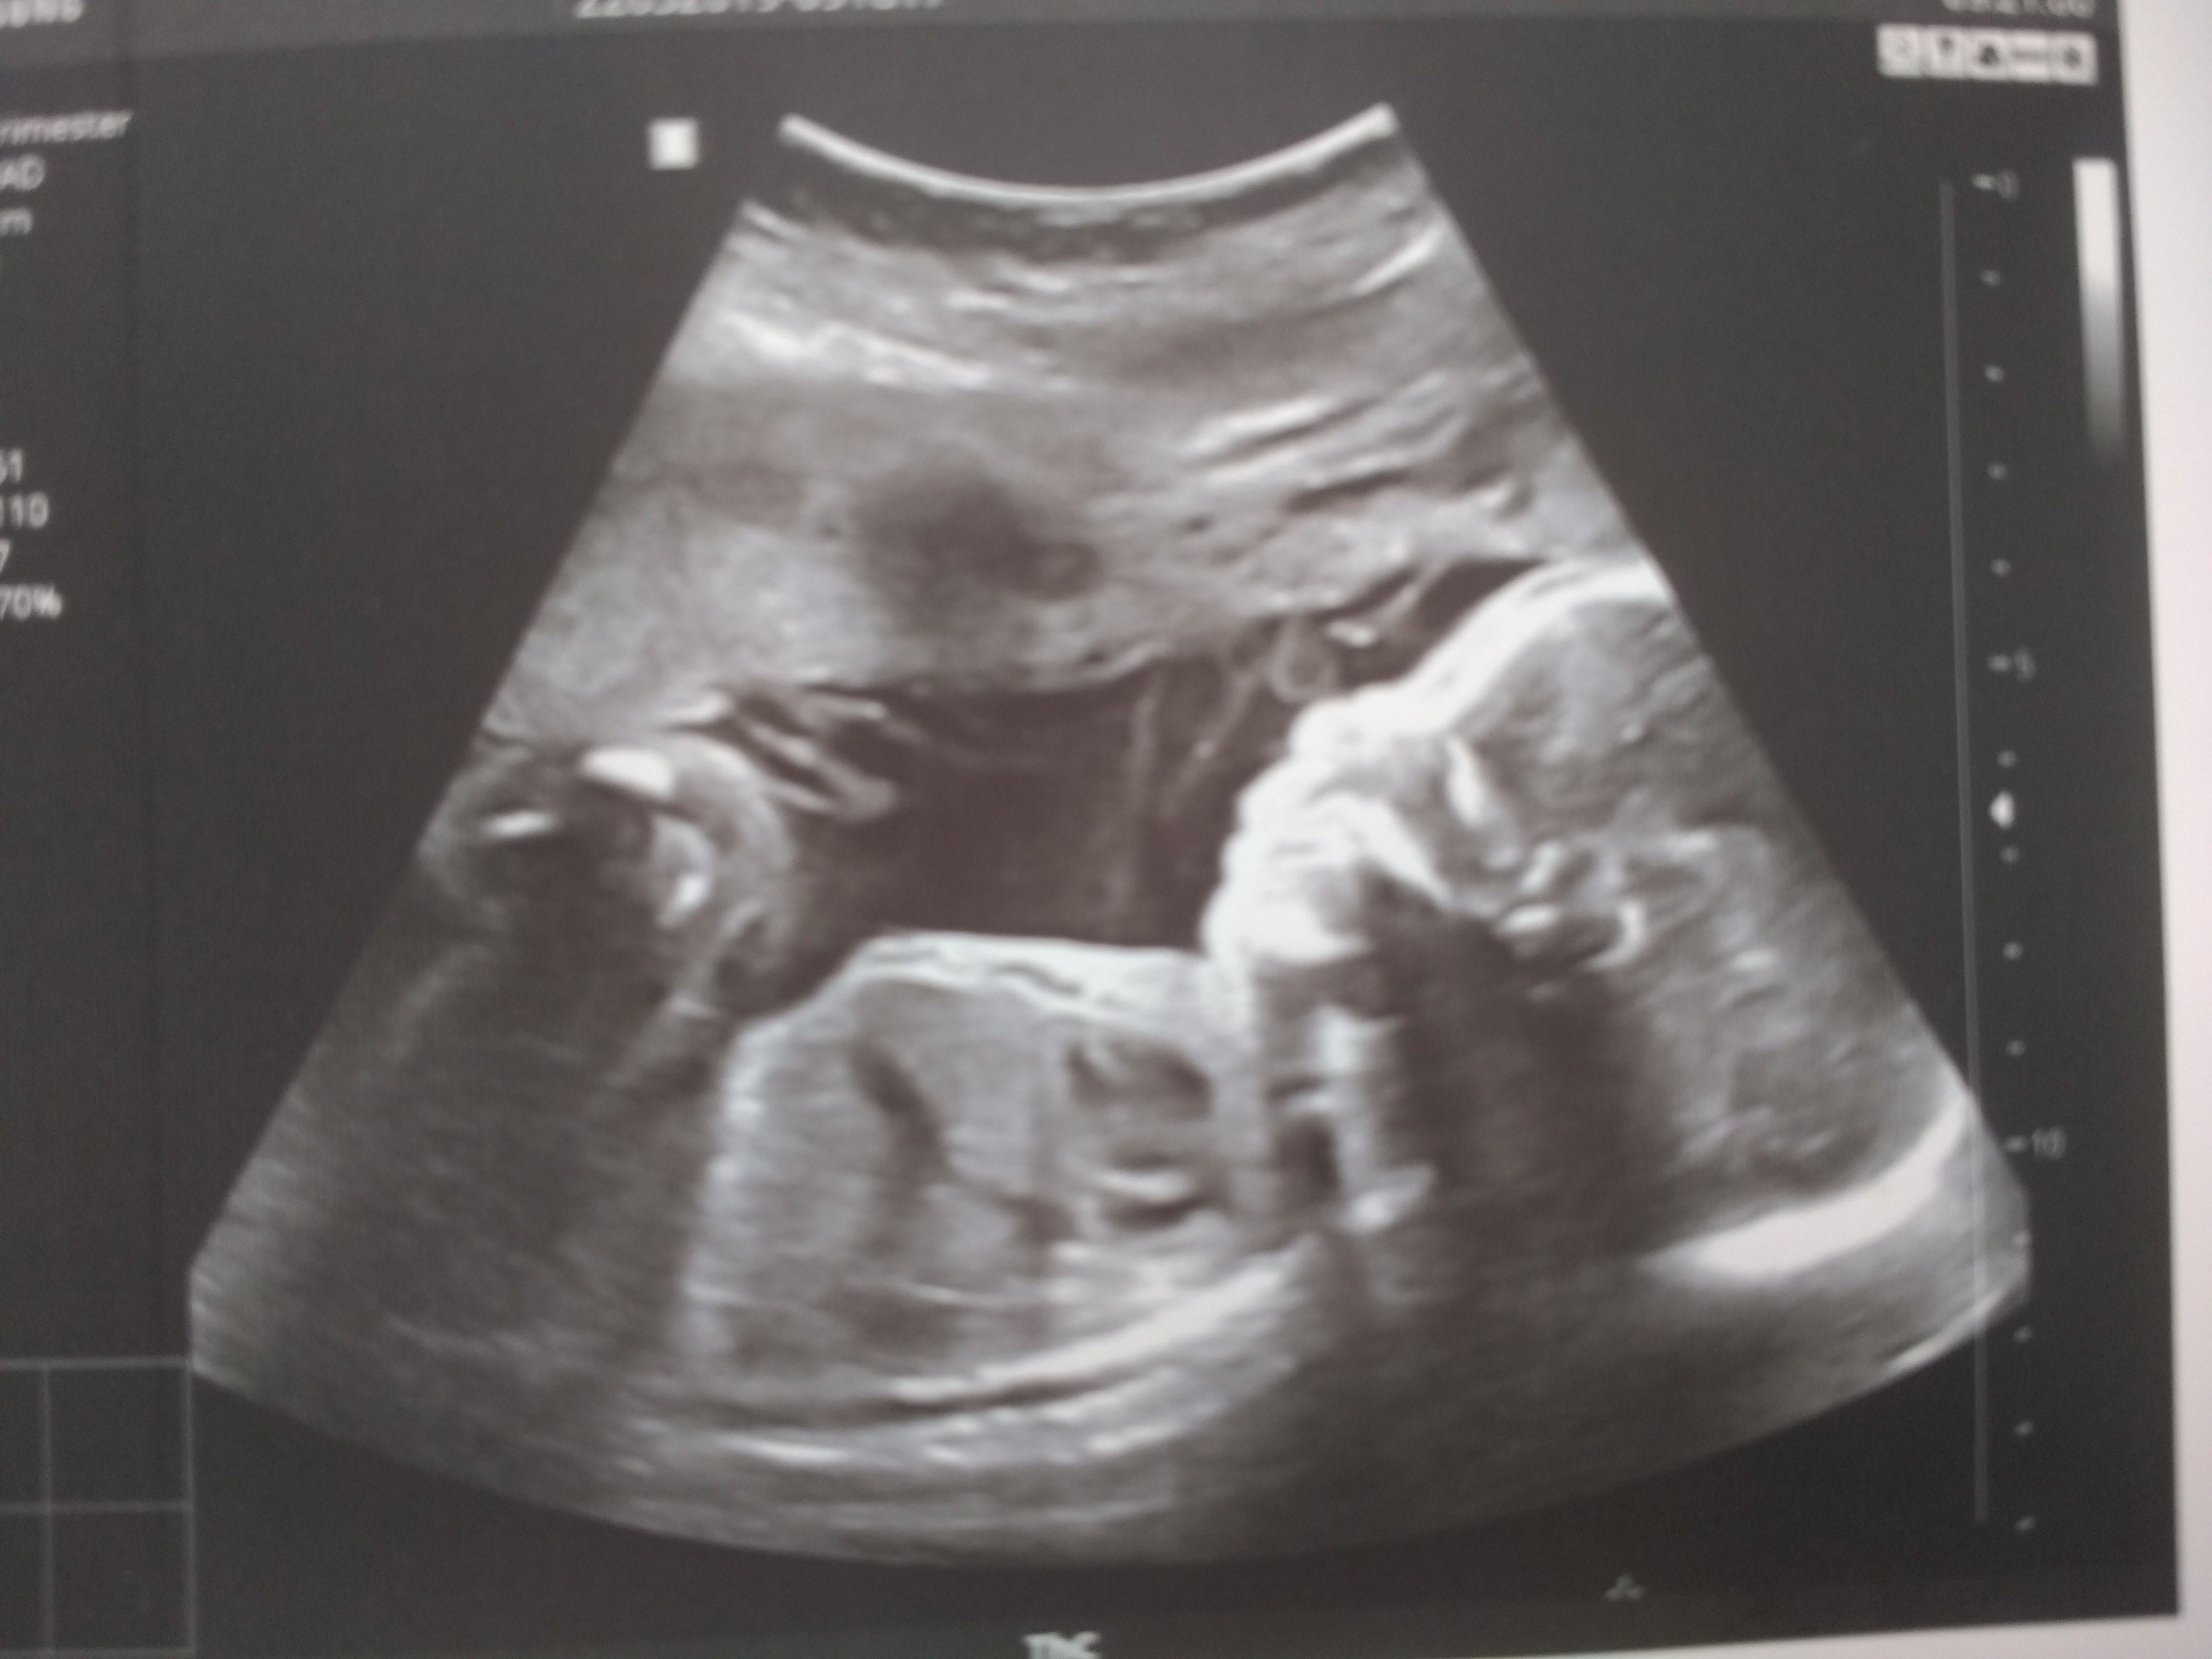

Moja mała akrobatka 600 gr (wczoraj w nocy czkała na górze, dzisiaj rano główka na dole

).

Szyjka nie sprawdzona, wymiarów nie przyuważyłam, ale wszystko w porządku. Następna wizyta przed świętami, 18 kwietnia.